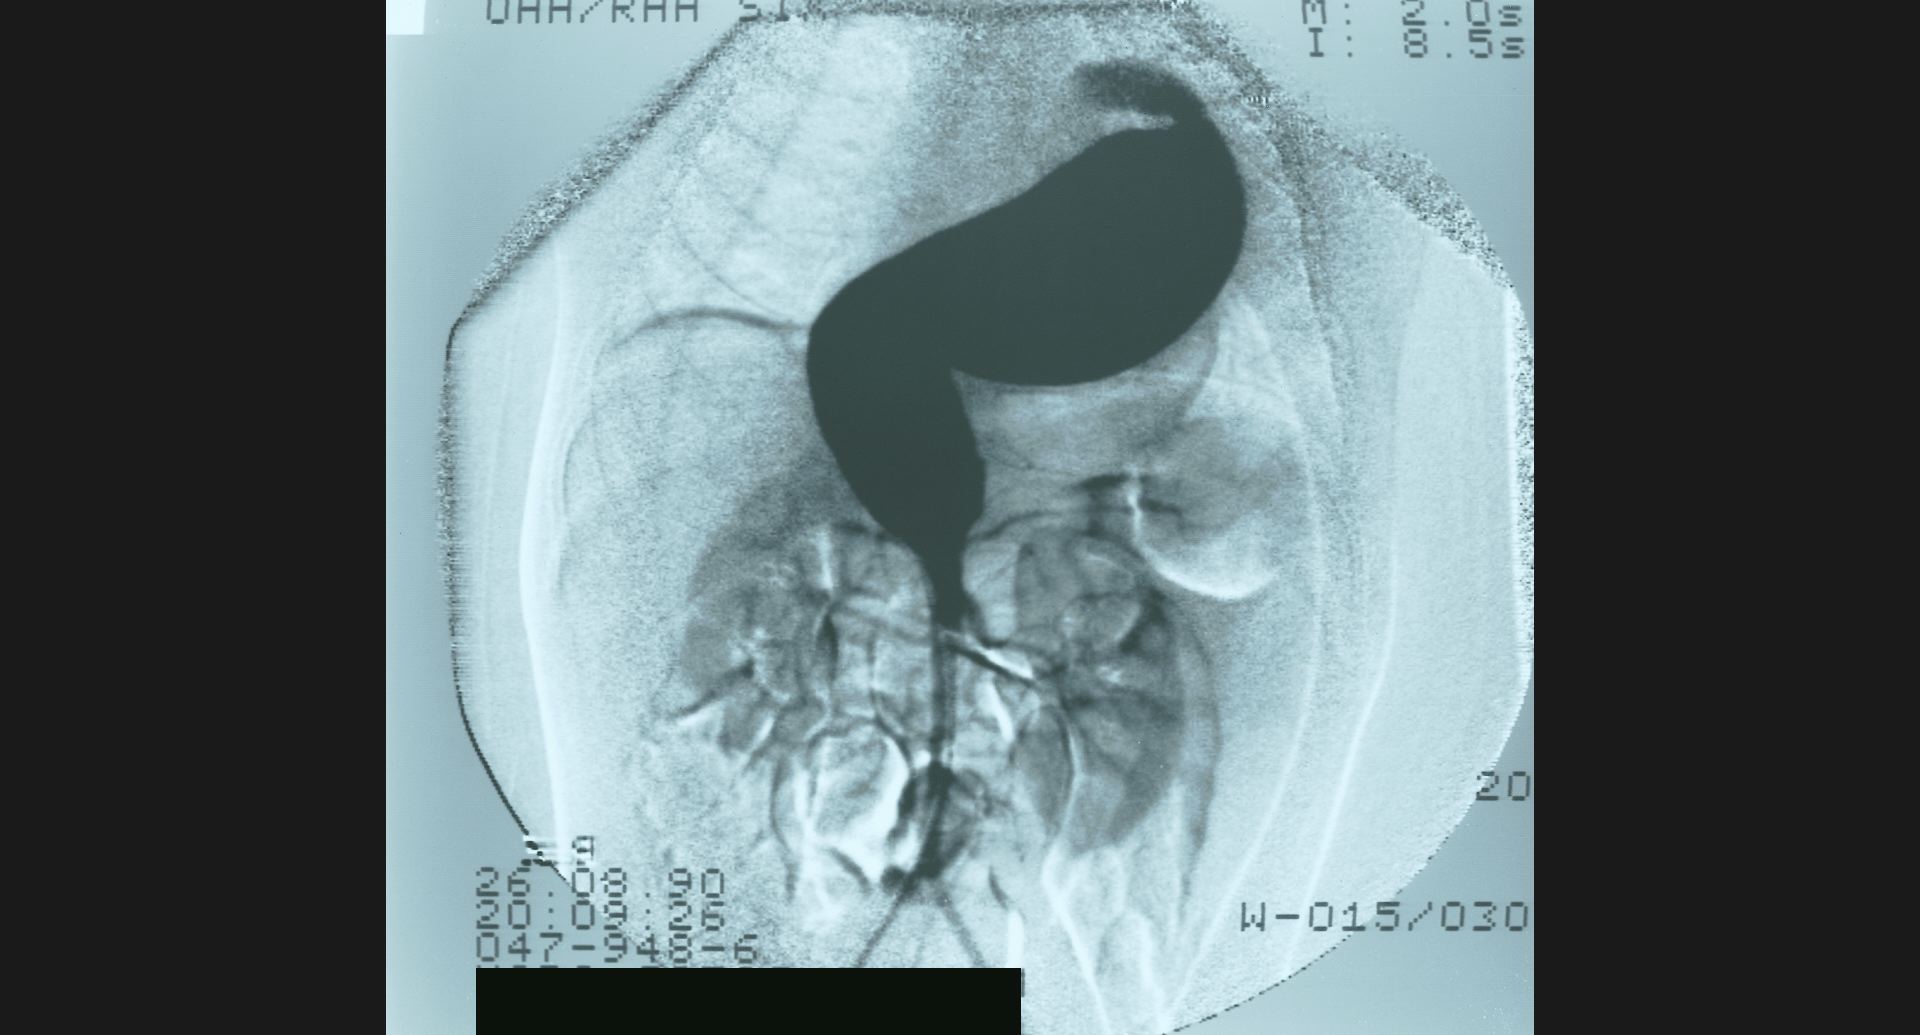

fig.10(99KB) :SMA thrombosis (angiography)

閉塞部位。腸管壁の細かい動脈。